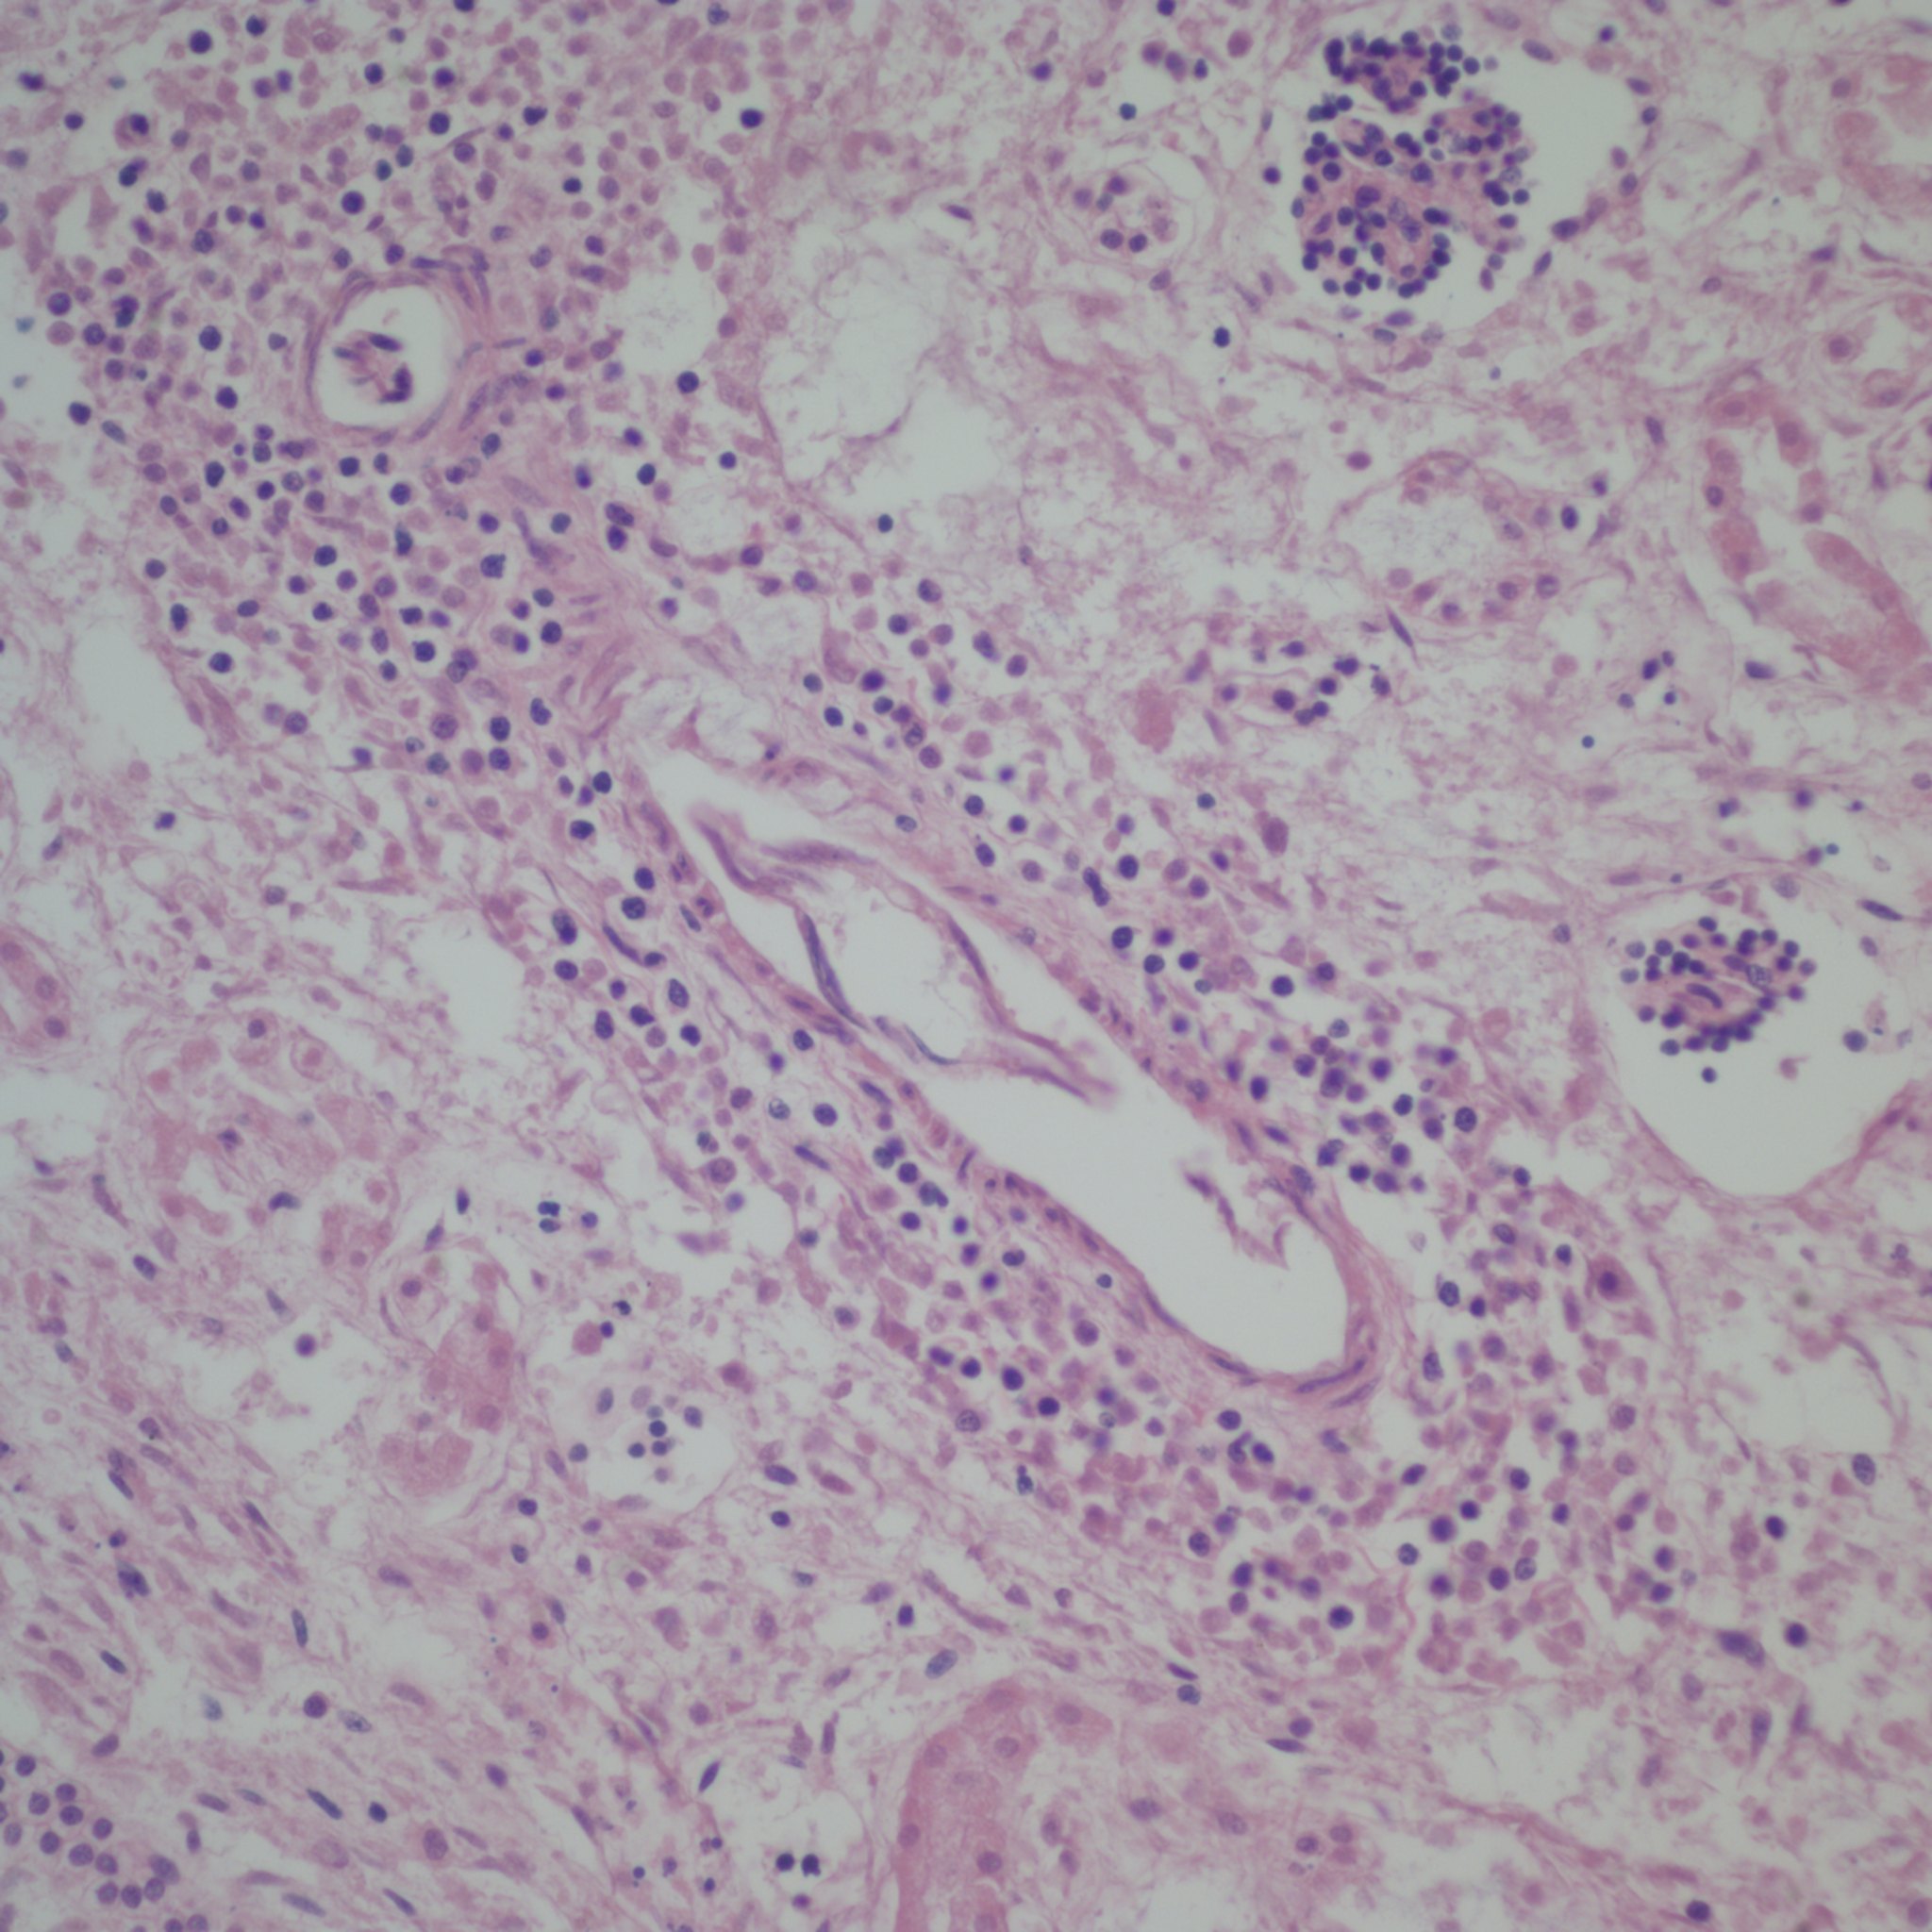

The thymus showed a modest loss of cortex microscopically and the adrenal could not be easily evaluated, and there was no frozen sample for fat staining, but the findings were not those of prolonged fetal stress as would have been expected in Rh alloimmunization. The kidney interstitium demonstrated plentiful hematopoiesis which appeared to account for the increase in weight. As is typical in the kidney, the hematopoietic response included myelopoiesis (Fig 4). The enlarged spleen was due to a cellular infiltration not just congestion, but the autolysis compromised interpretation. An iron stain highlighted a diffuse distribution of hemosiderin macrophages that were no very evident on H&E stain (Fig 5).

[caption id="attachment_58" align="alignnone" width="300"]

Spleen, left H&E 20x, right iron stain 40s showing pale hemosiderin macrophages.

Kidney showing hematopoiesis around a vessel, H&E 20x[/caption]